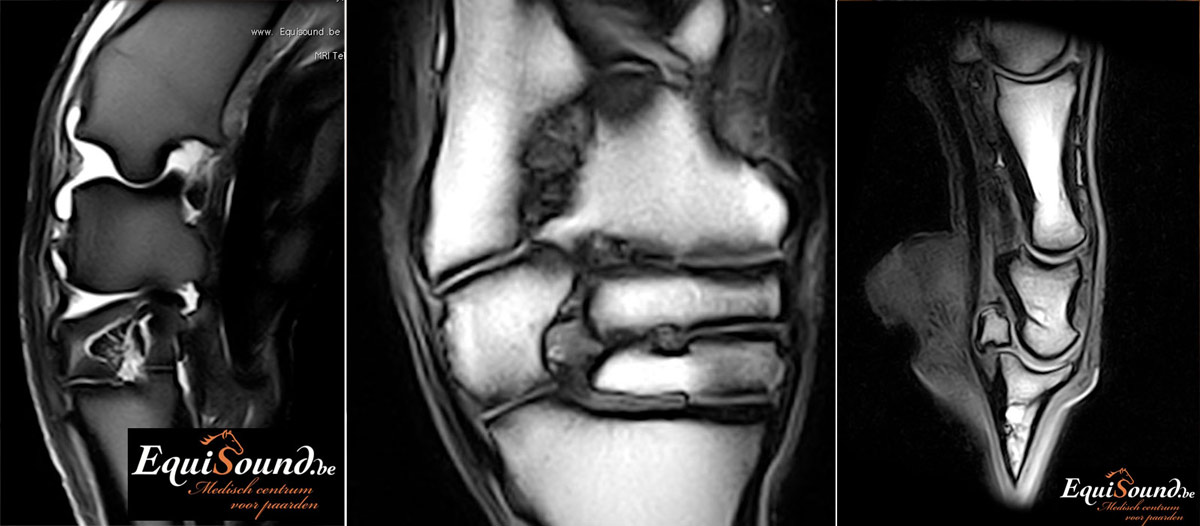

Voorbeeld

Dit paard had sinds enkele weken een unilaterale bloederige neusvloei. Op endoscopisch onderzoek was slechts een minimale afwijking ter hoogte van het linker ethmoid te zien. Bij radiografisch onderzoek was een grote massa in de sinus te zien. Er werd beslist een pre-operatieve MRI uit te voeren om de operatie te plannen en ook prognose beter te kunnen inschatten. Het ethmoid hematoom (PEH) bleek een groot deel van de linker sinus ingenomen te hebben.